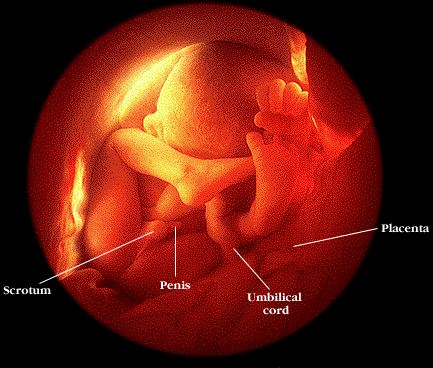

- Hjá drengjum eru eistun nú komin niður í pung.

- Barnið stjórnar nú sjálft líkamshita sínum.